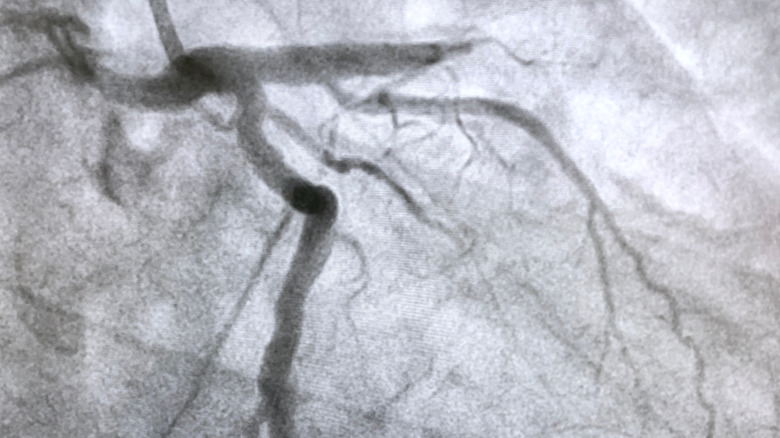

Acute coronary syndrome

Of course, when chest pain is felt, the first thing you may think of is heart attack — and that may very well be the cause. Heart attacks happen when a portion of heart muscle fails to receive adequate blood flow. Medical professionals broadly classify this as acute coronary syndrome, or, ACS (via Mayo Clinic). This can lead to tissue death that impacts the ability of the heart to do its job, leading to cardiac arrest and death of the patient. ACS can be broken down into myocardial infarctions (heart attacks) and a condition called unstable angina.

There are two types of myocardial infarction which, in general, are classified by how the present on electrocardiogram. These are ST elevated myocardial infarction (STEMI) and non-ST elevated myocardial infarction (NSTEMI), according to Merck Manuals. Both of these are very serious conditions. Unstable angina is a cousin of STEMI and NSTEMI and refers to chest pain that is neither relieved with rest nor a commonly prescribed drug called nitroglycerine. Unstable angina increases the risk of developing STEMI or NSTEMI and therefore should be investigated immediately.

Classically, the pain from ACS is described as an extreme pressure on the center of the chest, sometimes radiating to the arms. Sweating, clammy skin, and an impending sense of doom have also been described. However, not everyone with ACS experiences these symptoms. Women are more likely to describe atypical symptoms such as nausea or dizziness along with a general discomfort in the chest. ACS requires immediate treatment in the hospital in order to decrease the risk of death.